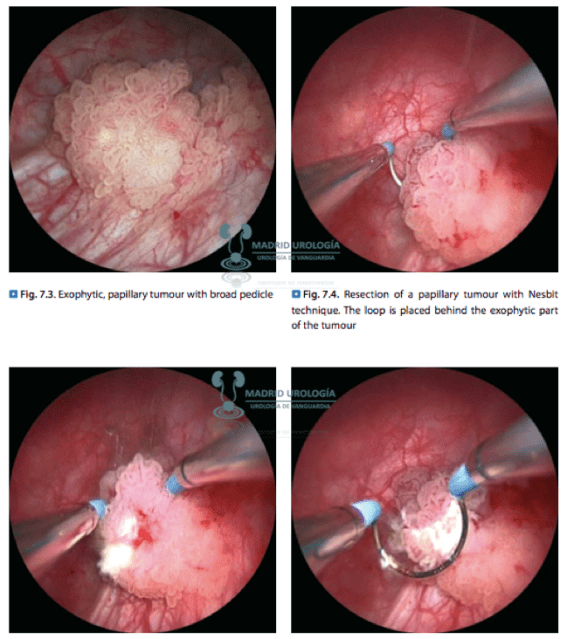

| La técnica de resección de la vejiga fue descrita por Nesbit en el año 1943. |

Las lesiones grandes deberían ser resecadas en varios tiempos enviandose muestran separadas para el estudio. Se dará información detallada de cada frasco en el cual se deberá identificar la base tumoral y según las guías incluso los bordes de la lesión.

La extensión de la lesión debería alcanzar un margen de al menos 2 cm, debido a que evidencia anatomopatológica, demuestra que el crecimiento tumoral puede alcanzar esta distancia de penetración lateral. ***

En principio toda resección debe realizarse en profundidad hasta por lo menos alcanzar la grasa que se ve entre las fibras musculares y el tejido perivesical. ***